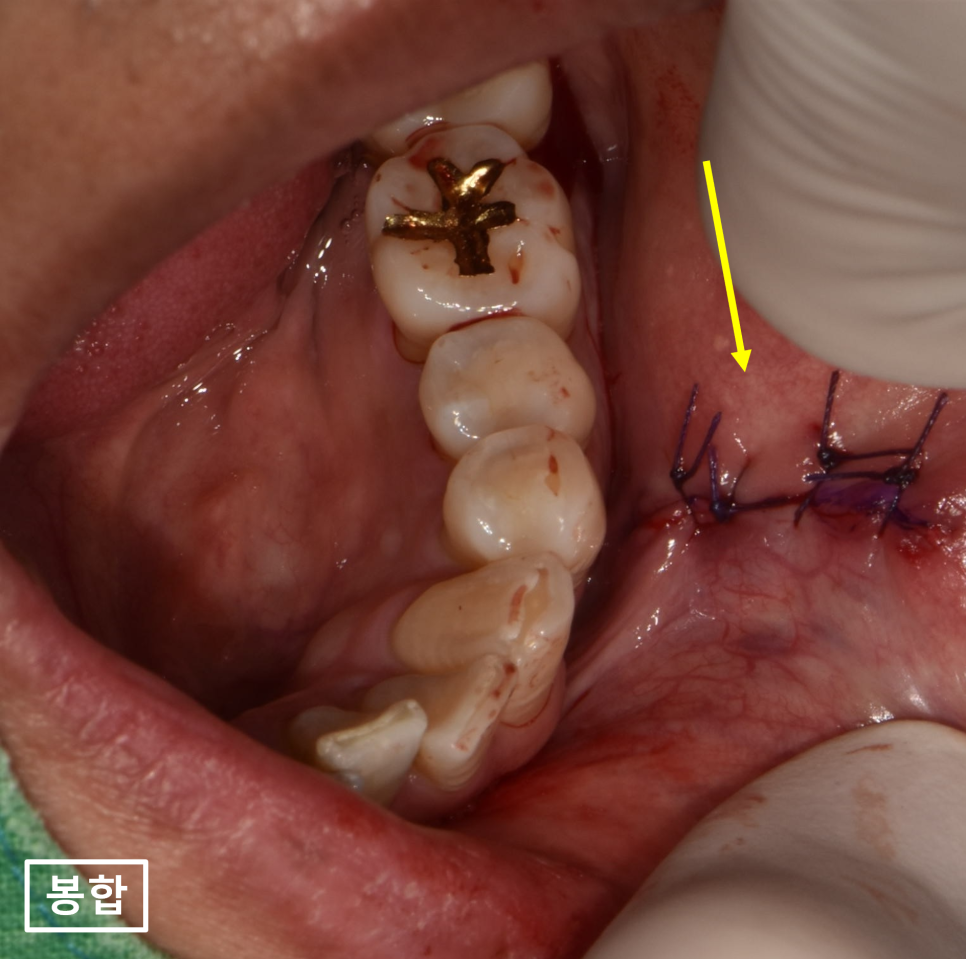

23.12.01(물혹제거) – 43y 김OO님

매산동치과 바른본에서 입술부음으로 내원하신

환자분의 입안물혹을 제거하고

봉합까지 완료한 사진입니다.

접근이 굉장히 어려워서

입술을 많이 당기면서 수술을 하느라

환자분께서도 고생을 하셨지만

수술은 굉장히 잘 됬습니다.